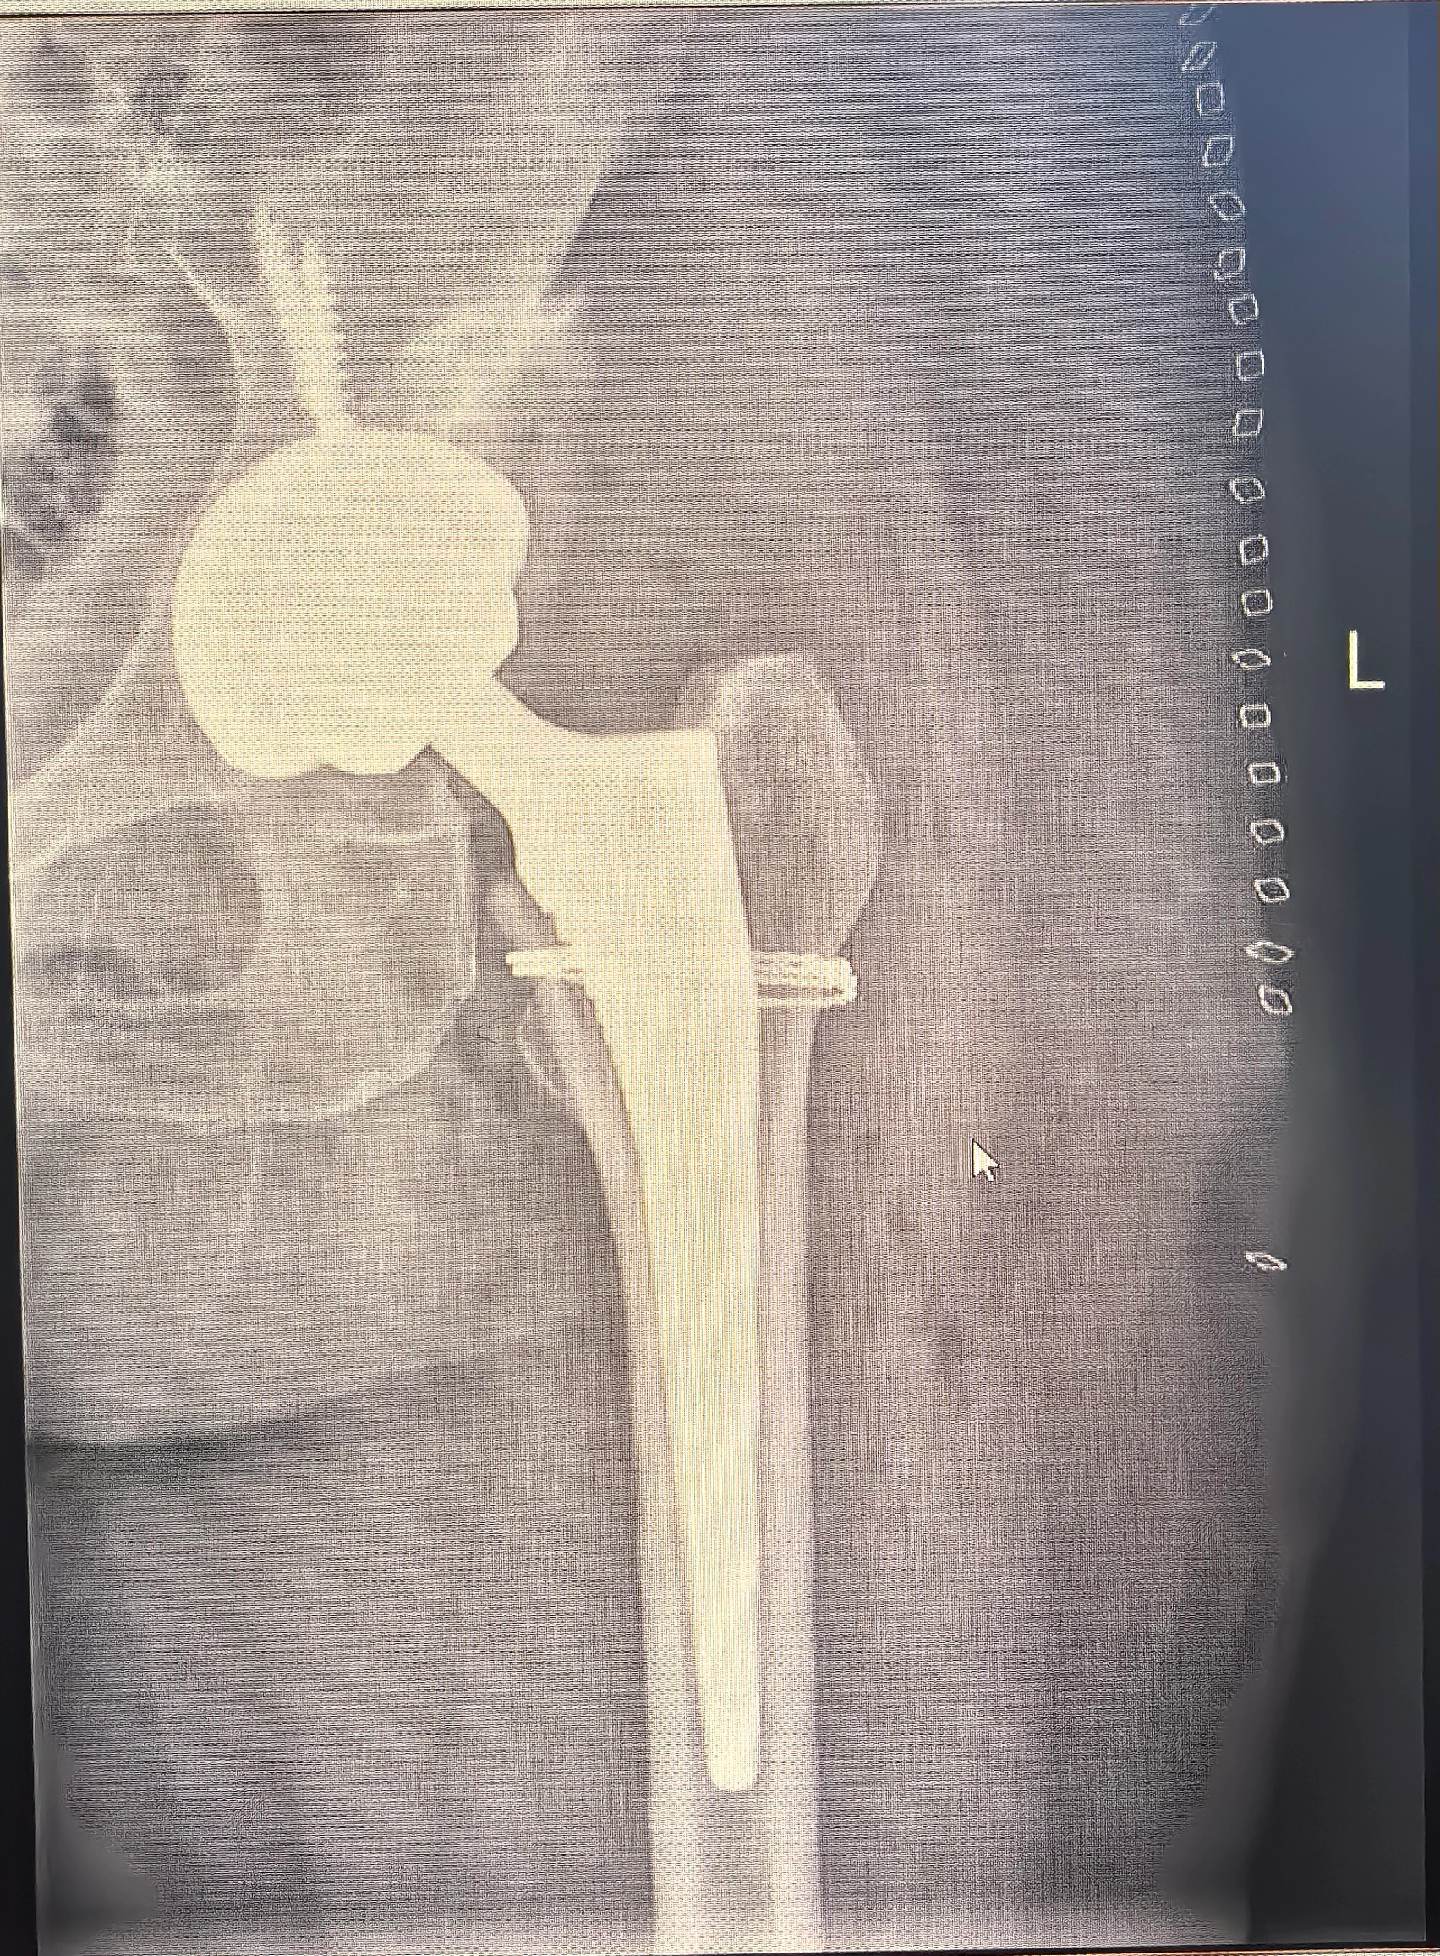

DDH,髋关节置换,髋关节发育不良。DDH髋关节置换,术前备的垫块,术中适当增加臼杯磋磨深度后包容性>80%,所以就没再放垫块,以最少的花费和最小的损伤让病人“髋”心🌹